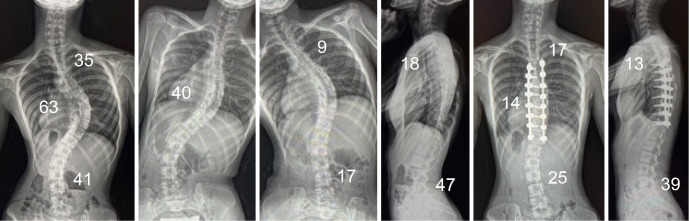

Abstract Image